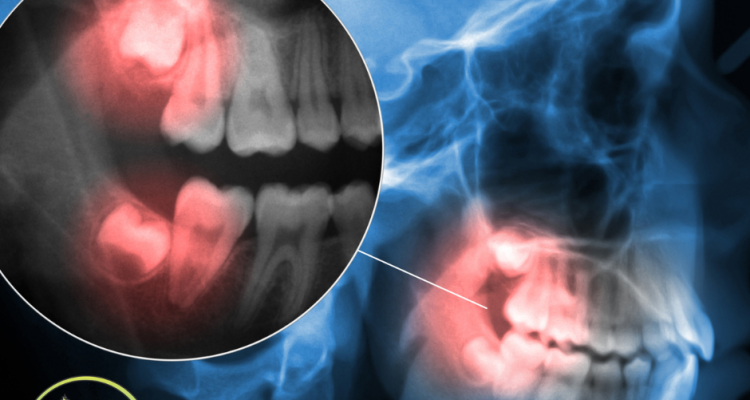

Tag: tooth crowding